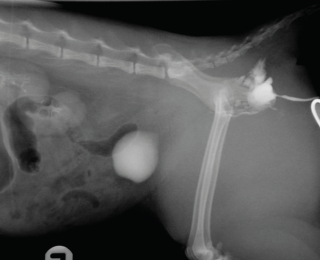

Many causes of dyspnoea are possible, and localisation is key in determining the required intervention. Thoracic trauma is common in these patients, even when there are no other visible injuries. Respiratory rate alone should not be used to exclude significant thoracic trauma and ideally survey radiographs should be performed in all patients (Figures 1 and 2) (Sigrist 2004). Table 1 gives some possible physical examination abnormalities with differentials and suggestions for diagnostics.

Pelvic trauma is a common finding in feline blunt-trauma patients and survey radiographs are recommended, even in ambulatory cats (Figure 9). Crepitus on manipulation of the pelvic limbs or palpation of fractures directly via rectal examination can provide an initial indication. Sacroiliac, coxofemoral and distal joint luxations, as well as long bone fractures are also fairly common and may be evident on physical examination or can be assessed on survey radiographs. The abdomen should also be carefully palpated for subtler abdominal wall ruptures (Figure 10).